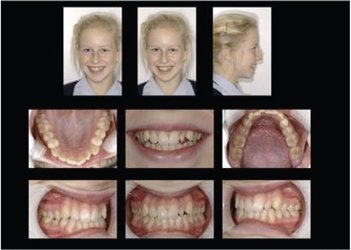

Early Orthodontics (The "Magic Window" Ages 8–10)

Starting orthodontic care young can guide jaw development, address crowding or bite issues, and sometimes reduce the need for treatment later. We recommend an assessment if your child has missing adult teeth, spacing concerns, or an over/underbite.

Teen orthodontics

Traditional braces and modern aligners give teens reliable results. Ceramic (tooth-coloured) braces are available for a less noticeable option.

Adult orthodontics – straighten, bleach & bond

Cosmetic orthodontics combines tooth straightening with whitening and bonding to deliver a complete smile makeover. Perfect for adults wanting straighter teeth and a brighter, more youthful smile.